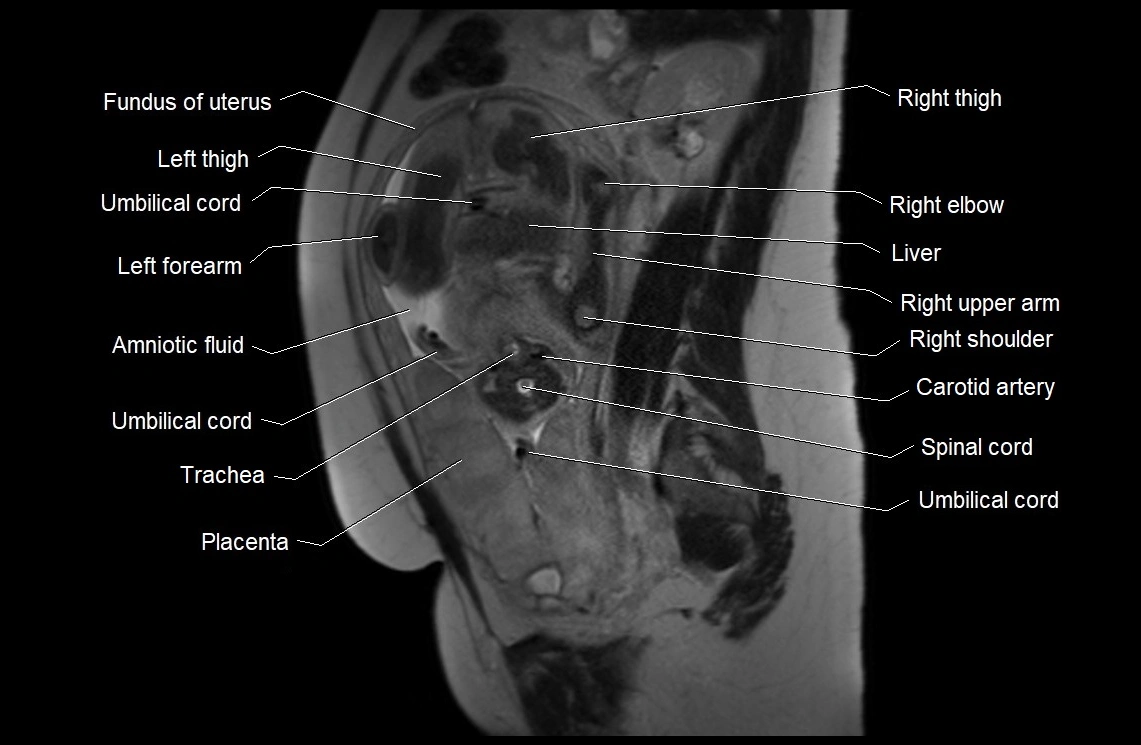

Amniotic fluid is the protective liquid surrounding the fetus within the amniotic sac. It plays an essential role in cushioning the fetus, enabling fetal movement, maintaining temperature stability, and allowing for normal lung and musculoskeletal development.

The volume and composition of amniotic fluid change throughout pregnancy. It is mainly derived from maternal plasma in early pregnancy, while in later stages, it consists largely of fetal urine, lung secretions, and transmembrane exchanges.

• Imaging relevance: MRI used for fetal visualization and assessing oligohydramnios/polyhydramnios when ultrasound is inconclusive

MRI Appearance

T2 HASTE (T2 GRE):

• Amniotic fluid shows very bright hyperintense signal

• Provides natural contrast against fetus and placenta

• Small particles (vernix) may appear as scattered hypointense foci within bright fluid

MRI image

image